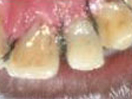

Dead discolored tooth

with a growth in bone